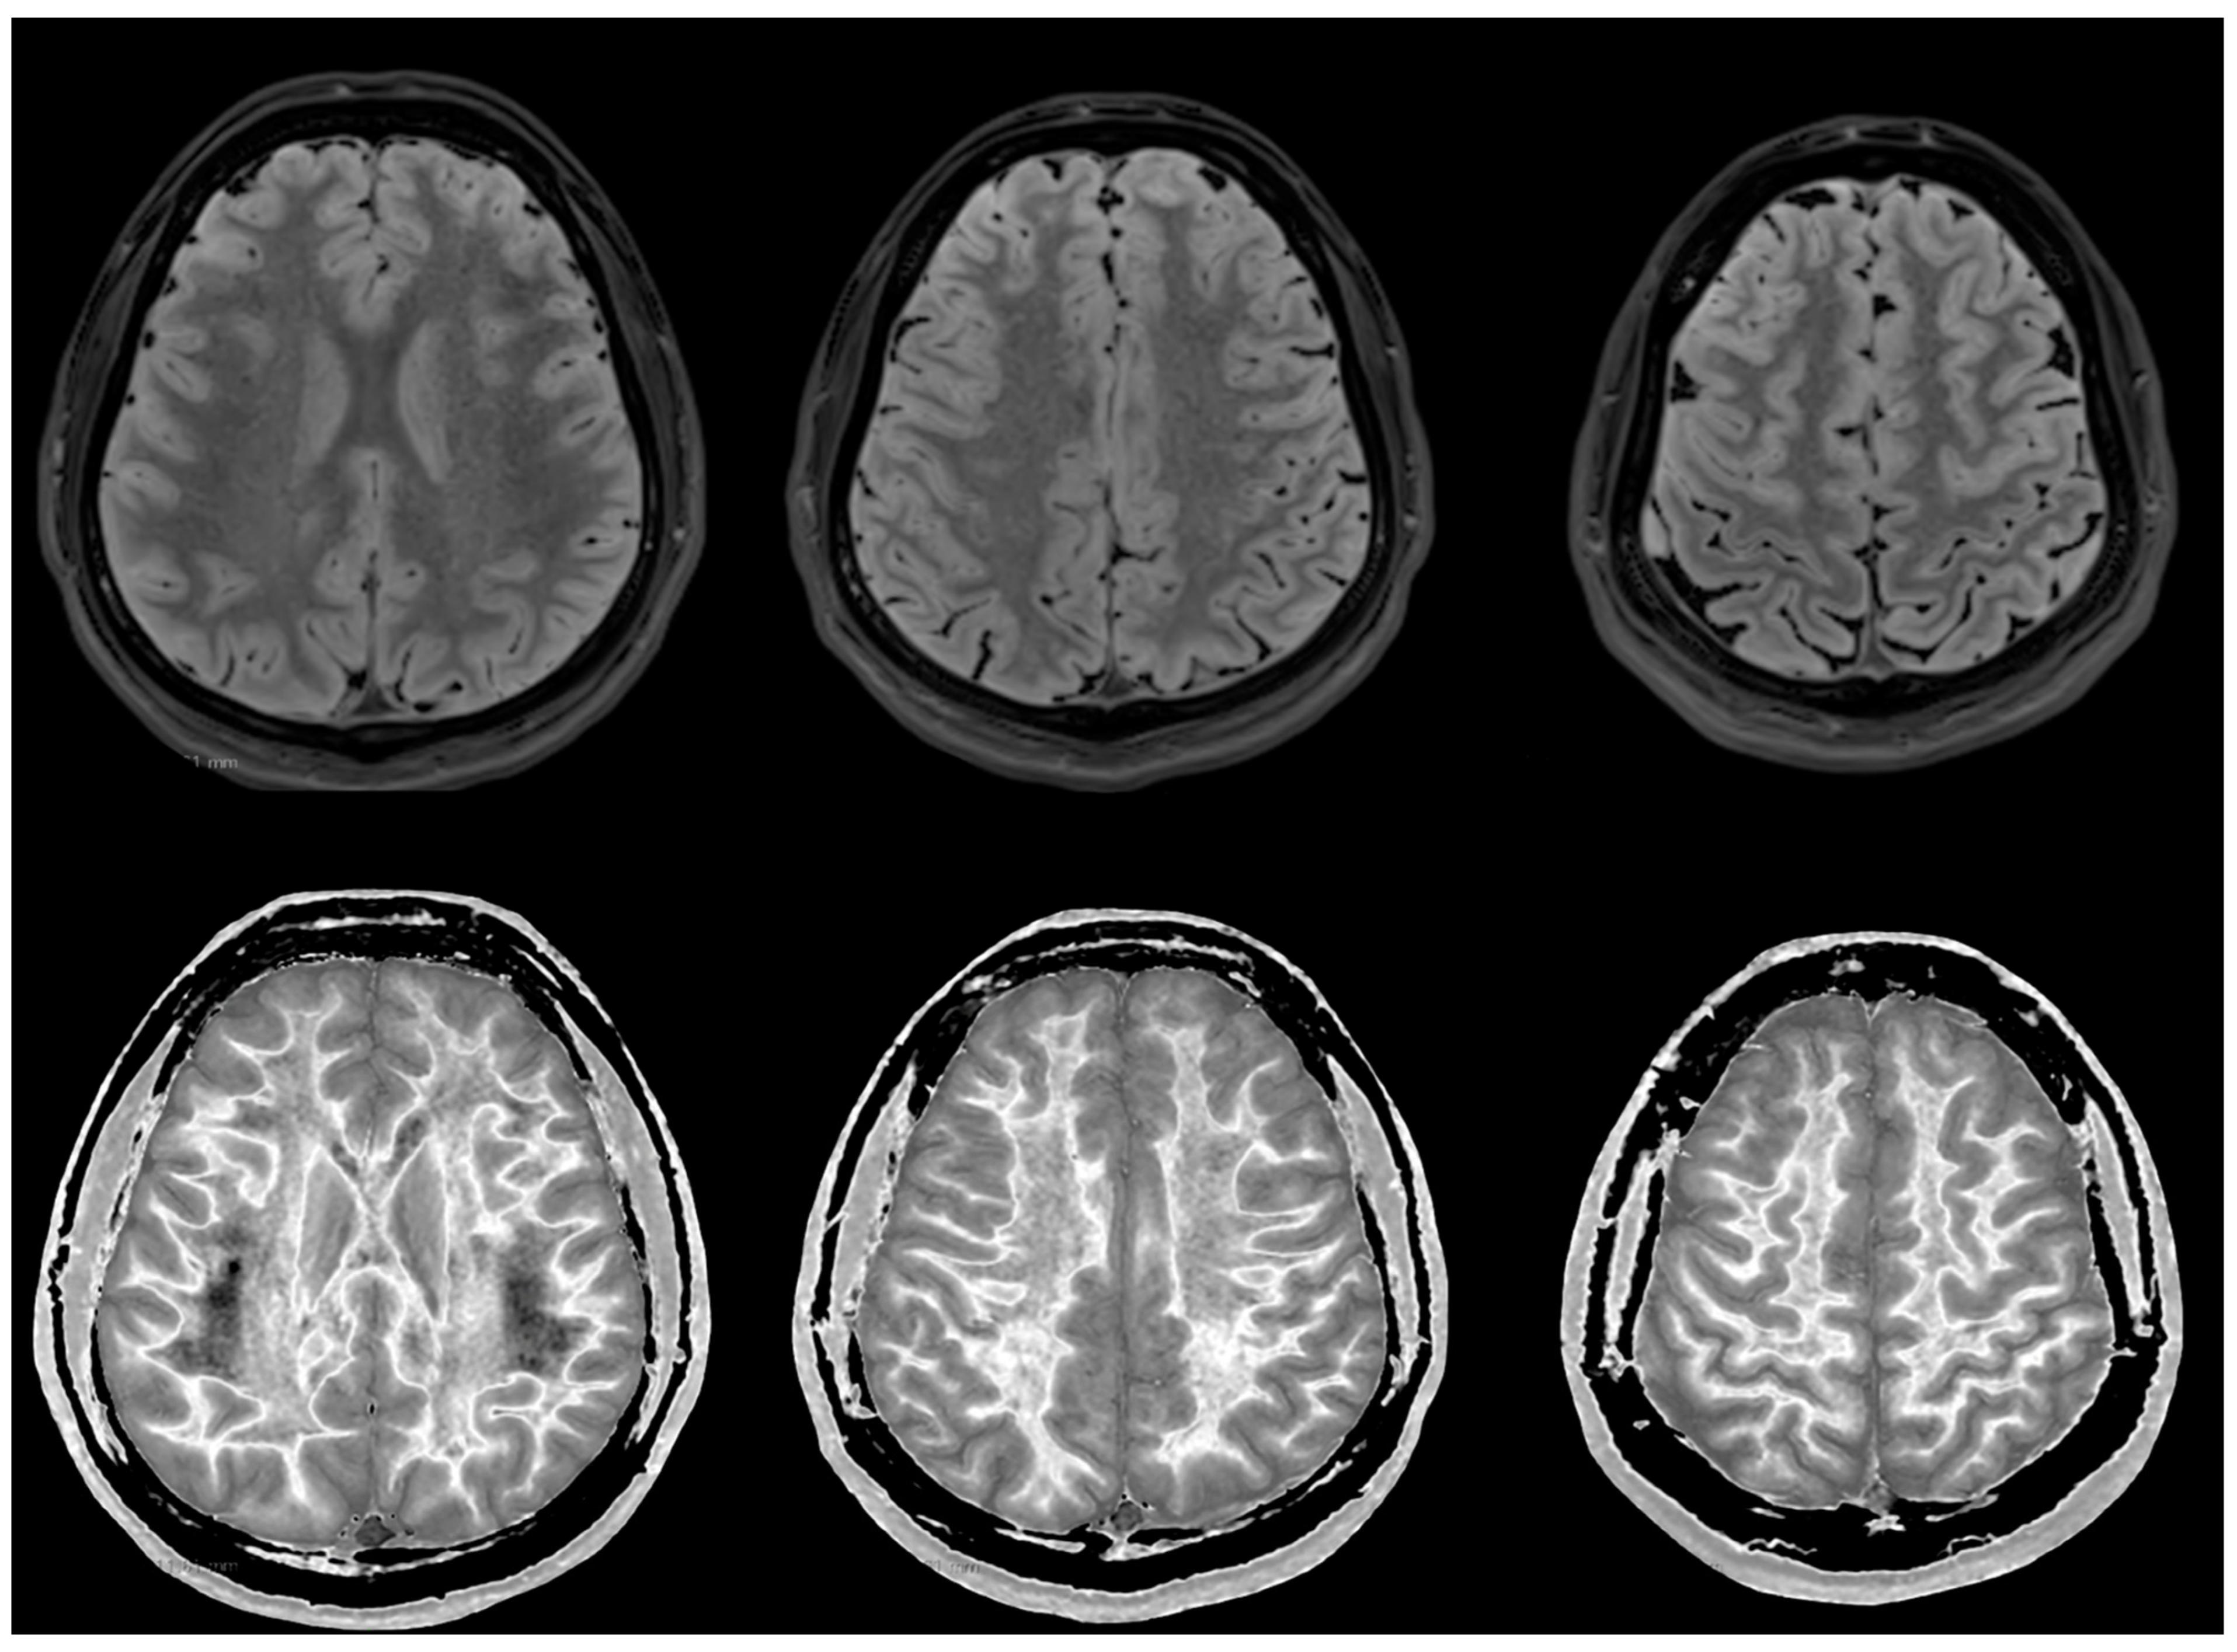

Figure 6 and Figure 7 show T2-FLAIR images (upper rows) with positionally matched dSIR images (lower rows). No abnormalities are seen in the white matter on the T2-FLAIR images, but very extensive high signal abnormalities are seen in the white matter of the corresponding dSIR images. There is relative sparing of the anterior central corpus callosum and, to a lesser extent, the posterior central corpus callosum. There is also some sparing of the peripheral white matter in the cerebral hemispheres.

Overall, the MRI findings in Case 2 are very similar to those in Case 1, as shown in Figure 4 and Figure 5. They have been described as a whiteout sign. This often involves 80% or more of the white matter in the cerebral and cerebellar hemispheres having an abnormal high signal appearance.

Figure 6. Case 2 was examined two years after his asphyxial episode. Comparison of positionally matched T2-FLAIR images (upper row) and narrow mD dSIR images (lower row). No abnormality is seen on the T2-FLAIR images, but there are extensive areas of high signals in the white matter of the brain. The anterior and posterior central corpus callosum and parts of the frontal lobes have a lower, more normal signal (darker appearance). Horizontal CSF flow artefacts are seen in the dSIR image in the middle lower row.

Figure 7. Case 2 was examined two years after his asphyxial episode. Comparison of positionally matched T2-FLAIR images (upper row) and narrow mD dSIR images (lower row). No abnormality is seen on the T2-FLAIR images, but there are extensive areas of high signals in the central white matter of the brain (lower row). Only some of the peripheral white matter on the lower images appears darker and looks more normal on the dSIR images.